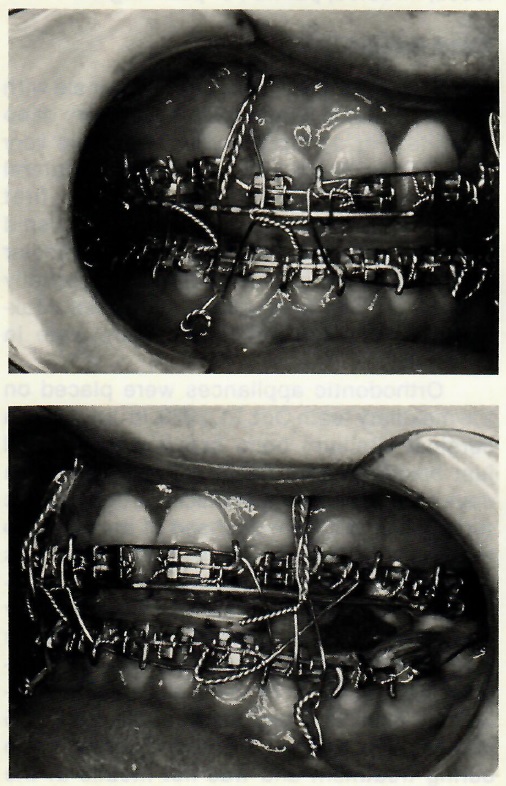

Overlay Surgery Wire

This technique can save the orthodontist a considerable amount of time in cases on which segmental maxillary surgery is to be performed in conjunction with orthodontic treatment. Normally, it has been necessary for the orthodontist to be present in the operating room to replace the archwire with a stabilizing archwire once the maxillary segments were repositioned.

An easier approach, in cases in which maxillary bicuspids are to be removed, is to bend an .045" or .052" overlay archwire to the exact length that the arch will be after the bicuspids have been removed and the maxillary components repositioned. Prior to the surgery appointment, the main archwire is cut in the bicuspid areas.

After the oral surgeon repositions the segments, he inserts the overlay wire into the headgear tubes and ties it to the main archwire. This makes for a good postsurgical stabilization and eliminates the need for the orthodontist to be present in the operating room.

The same procedure can be used in cases of maxillary segmental surgery in which no bicuspids are removed.

Fig. A